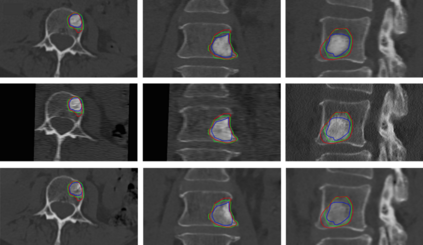

Accurate and reliable registration of longitudinal spine images is essential for assessment of disease progression and surgical outcome. Implementing a fully automatic and robust registration is crucial for clinical use, however, it is challenging due to substantial change in shape and appearance due to lesions. In this paper we present a novel method to automatically align longitudinal spine CTs and accurately assess lesion progression. Our method follows a two-step pipeline where vertebrae are first automatically localized, labeled and 3D surfaces are generated using a deep learning model, then longitudinally aligned using a Gaussian mixture model surface registration. We tested our approach on 37 vertebrae, from 5 patients, with baseline CTs and 3, 6, and 12 months follow-ups leading to 111 registrations. Our experiment showed accurate registration with an average Hausdorff distance of 0.65 mm and average Dice score of 0.92.